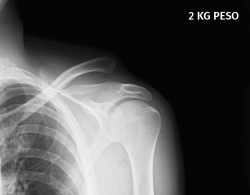

Figura 2. Inserción de las agujas-guía en el extremo clavicular al comienzo de la intervención en que los relieves óseos son fácilmente apreciables. Hombro derecho.

La técnica artroscópica empleada fue la denominada de cerclaje de suspensión cortical coracoclavicular(2). Por encontrarnos más habituados, empleamos la posición de decúbito lateral y los portales de artroscopia posterior, anterolateral y 2 portales anteriores realizados para abordar el espacio subcoracoideo bajo visión directa, según la técnica descrita(5,6,7). En los 6 primeros casos empleamos el dispositivo AC TightRope® (Arthrex, Inc., Naples, Florida). A pesar de su analogía, pero motivado por el cambio de diseño realizado en dicho dispositivo y por el menor orificio requerido, en los 16 restantes casos hemos utilizado el dispositivo AC EndoButton TwinBrigde® (Smith & Nephew, London, England). En los casos con lesiones acompañantes, se emplearon los dispositivos OsteoRaptor 2,3® (Smith & Nephew, London, England) para la reconstrucción de las lesiones de tipo SLAP y el dispositivo TwinFix PK 5,5® (Smith & Nephew, London, England) para el tratamiento de las lesiones de los tendones del manguito rotador. En los últimos 6 casos hemos desestimado el empleo de las guías diseñadas para la implantación de estos dispositivos. Encontramos que su empleo es engorroso, dificulta la selección de los puntos de realización de los túneles óseos y prolonga el tiempo quirúrgico. Optamos por la inserción de las agujas-guía en el extremo clavicular al comienzo de la intervención (Figura 2). En este momento los relieves óseos son fácilmente apreciables. La selección del punto en el cuello de la coracoides se realiza de forma percutánea bajo visión directa (Figura 3). Tras realizar los túneles óseos por taladrado sobre las agujas-guía en la forma habitual, estos se conectan mediante un hilo Vicryl® n.º 2 (Ethicon Endo-Surgery Inc., Cincinnati, Ohio, United States) que hace de pasador final del dispositivo elegido (Figura 4). Si es necesario, se completa la reparación de la fascia trapeciodeltoidea y/o de la cápsula acromioclavicular superior a través del miniabordaje superior asociado.